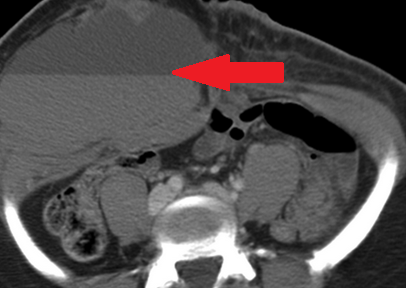

Αμφοτερόπλευρη αυτόματη νεφρική αιμορραγία — κοκκιωμάτωση Wegener (Ευγενική παραχώρηση Dr. V. Penopoulos)